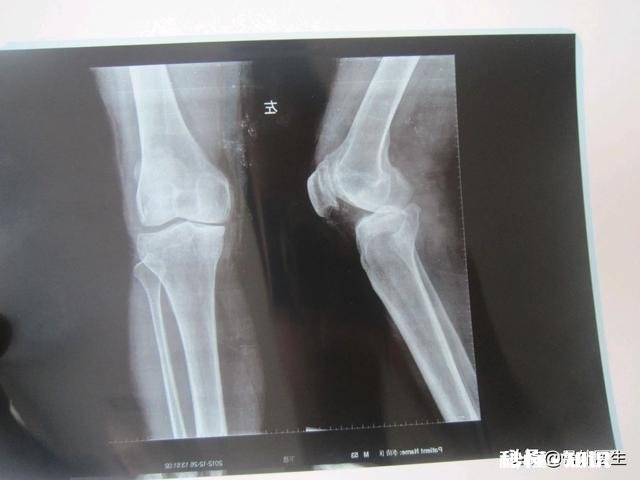

文章插图

半月板分布于膝关节内、外侧,半月板的作用就是可以使膝盖两骨关节面更为适应,以缓冲外力对关节的冲击和震动,还可以改变关节的运动形式,增大关节活动范围 。

解剖显示:关节软骨是位于关节腔内两关节面之间,膝关节软骨呈半月状,故有“半月板”之称 。而半月板的生理特点之一就是不可再生性 。所以机体各部位软骨的保护,永远大于患病后的修复 。

由于软骨本身没有血管和神经,所以初期磨损基本感觉不到什么痛苦,直到磨损到一定程度,软骨下的神经裸露时才有痛感,并且磨损的软骨杂质会堆积于关节周围,刺激周围组织发炎,加重关节疼痛 。